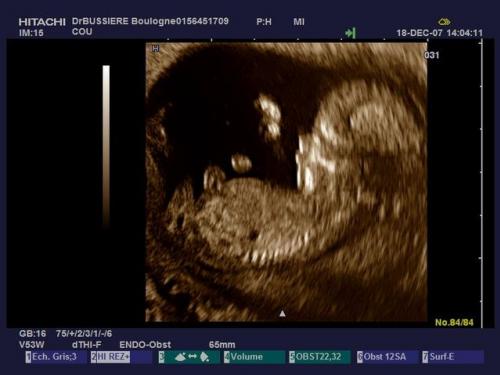

Battement coeur bebe fille garcon. Fille ou garçon. Mais je me surprends à chercher des indices là où il n y en a. Coucou j ai un petite question j ai entendu parler qu on pouvait savoir le sexe de bebe par rapport au battement de cœur par minute et qu ils faisaient comme ça dans le temps. Dans les temps anciens cette hypothèse avait une certaine part de probabilité car les gens remarquaient que dans le ventre de la mère le cœur des filles battait différemment du cœur des garçons.

Bonjour bb1 pour moi j ai eu une eco de datation avec 170 de battement de cœur par minute. Peut on vraiment savoir le sexe de bébé. Je ne sais pas si ca fonctionne réellement. Bien qu il n existe pas de test et de méthodes infaillibles certains signes pourraient vous mettre la puce à l oreille au fil des mois.

Battements du coeur. Selon vous filles ou garcon. Alors moi a 6 sa 3 son cœur battait a 127 bpm et a 8 sa 3 entre 160 et 180 bpm. Battement du cœur fille ou garcon.

Battement coeur foetus fille ou garcon. Deviner le sexe grâce au battement de cœur de bebe.